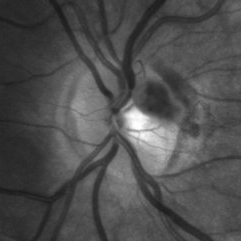

VHL "Free Floating" Juxtapapillary Hemangioblastoma

Jul 1 2014 by John S. King, MD

30-year-old female with fhx VHL and CNS hemangioblastomas and visceral lesions. P/C with a floater (no PVD or VH) after episodes of vomiting.

Photographer: Wayne A Ladlee Jr

Imaging device: Red Free

Condition/keywords: retinal hemangioblastoma, Von Hippel-Lindau